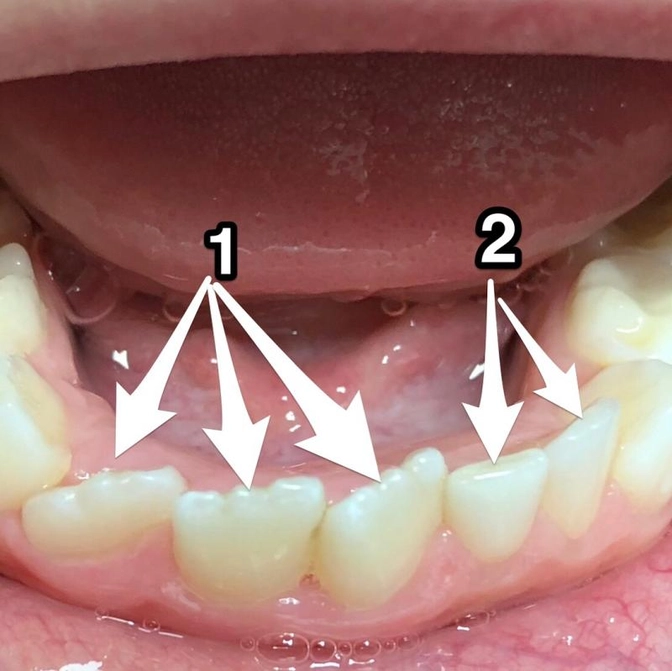

Ребёнку на фото - 7 лет

1. Зубы постоянные.

Их три.

Они намного крупнее молочных.

Край волнистый.

Но это у всех так.

Со временем станет ровным - слегка «подсотрётся».

2. А это молочные.

Их два.

Три+Два - всего Пять

А должно быть Четыре.

Молочных тоже было больше - пять.

Это называется - сверхкомплектный зуб.

Заложилось больше нормы.

Такое бывает.

И четкого объяснения этому явлению нет.